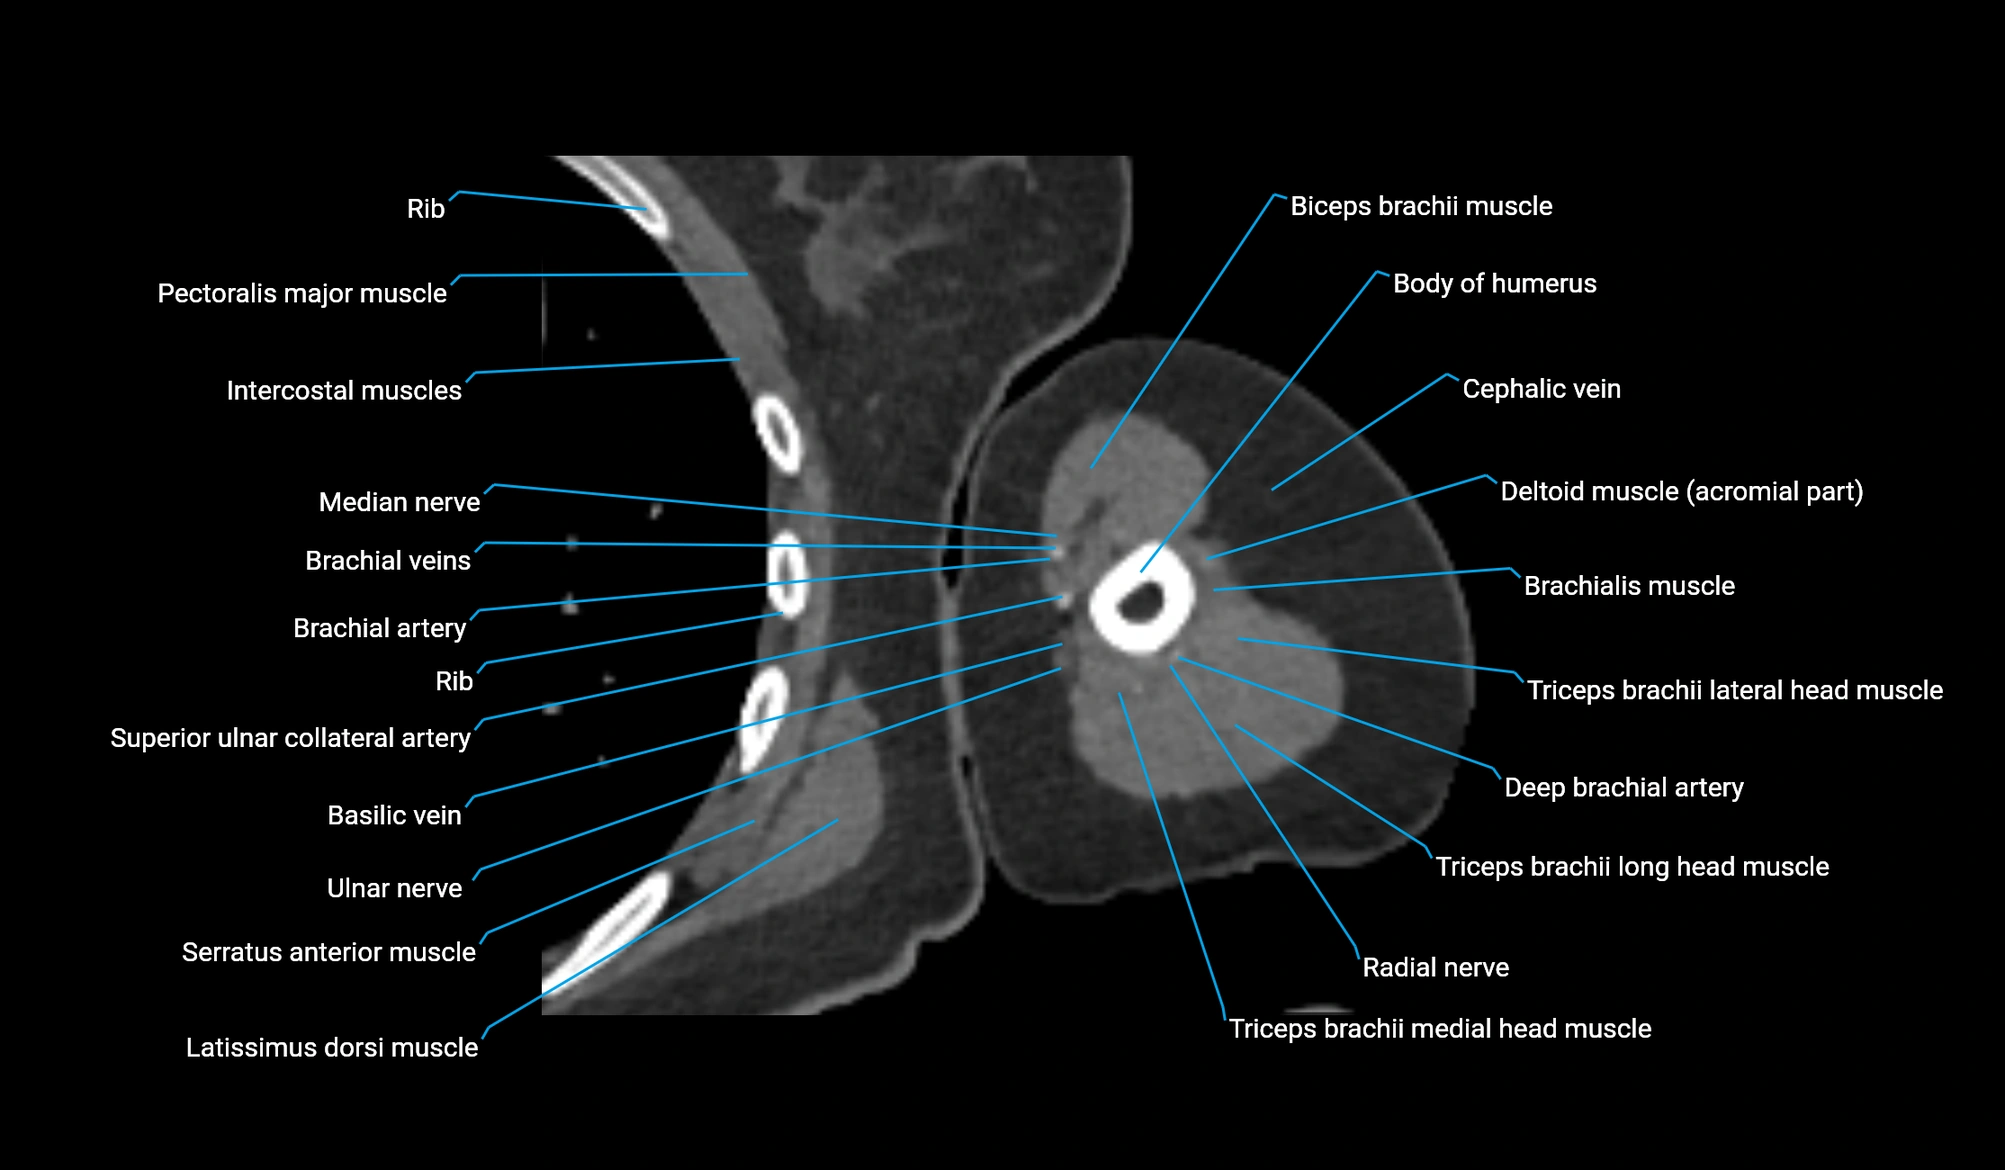

- Body of humerus

- Biceps brachii muscle

- Brachialis muscle

- Cephalic vein

- Brachial artery

- Deep brachial artery

- Long head of triceps brachii muscle

- Lateral head of triceps brachii muscle

- Medial head of triceps brachii muscle

- Radial nerve

- Superior ulnar collateral artery

- Basilic vein

- Median nerve

- Ulnar nerve

- Pectoralis major muscle